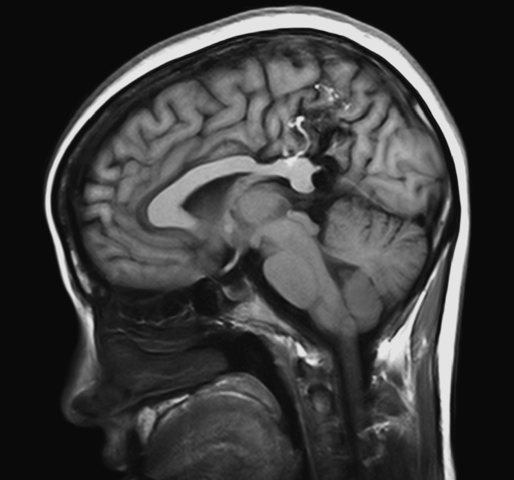

• Etiology: Testing

Etiology: Testing

Researchers in the 2000’s used medical testing of the EEG, CT, PET, and MRI to produce neuroimaging to try to better understand the cause of Autism. Heflin, J., Alaimo, D. (2007) . Students with Autism Spectrum Disorders. Upper Saddle River: Pearson